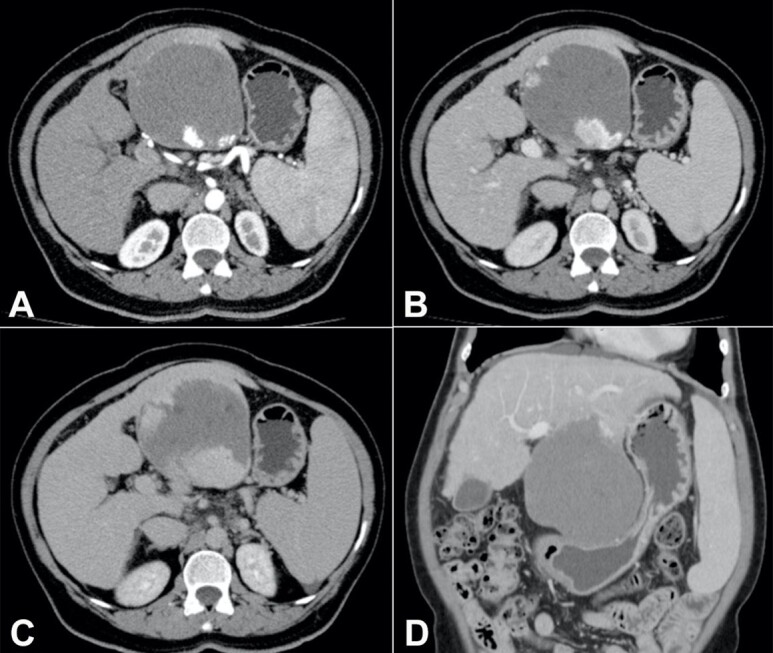

Giant hepatic hemangiomas are occasional in patients with cirrhosis. It remains a challenge to decide on the need for treatment and choose the most appropriate intervention. A 62-year-old woman was recently diagnosed with cirrhosis and complained of upper abdominal fullness, reduction in oral food intake, and weight loss of 6 kg over the last three years. Upper digestive endoscopy evidenced thin-caliber esophageal varices and significant extrinsic compression of the lesser gastric curvature. Abdominal computed tomography revealed an exophytic tumor in the left hepatic lobe, measuring 11.5 cm, which had progressive centripetal contrast enhancement from the arterial phase, compatible with hepatic hemangioma. Serum tumor markers were negative, and her liver function was unimpaired. The patient underwent surgical resection (non-anatomical hepatectomy of segments II and III) which had no immediate complications, and the histopathological evaluation confirmed cavernous hepatic hemangioma. Two weeks later, she was admitted to the emergency room with jaundice, signs of hepatic encephalopathy, and moderate ascites, and was further diagnosed with secondary bacterial peritonitis. As no perforations, abscesses, or fistulas were observed on subsequent imaging tests, clinical management was successfully carried out. This case highlights that giant hepatic hemangiomas may be symptomatic and warrant treatment. In the setting of cirrhosis and portal hypertension, physicians should be aware of the risk of hepatic decompensation following surgical resection, even in patients with Child-Pugh class A.